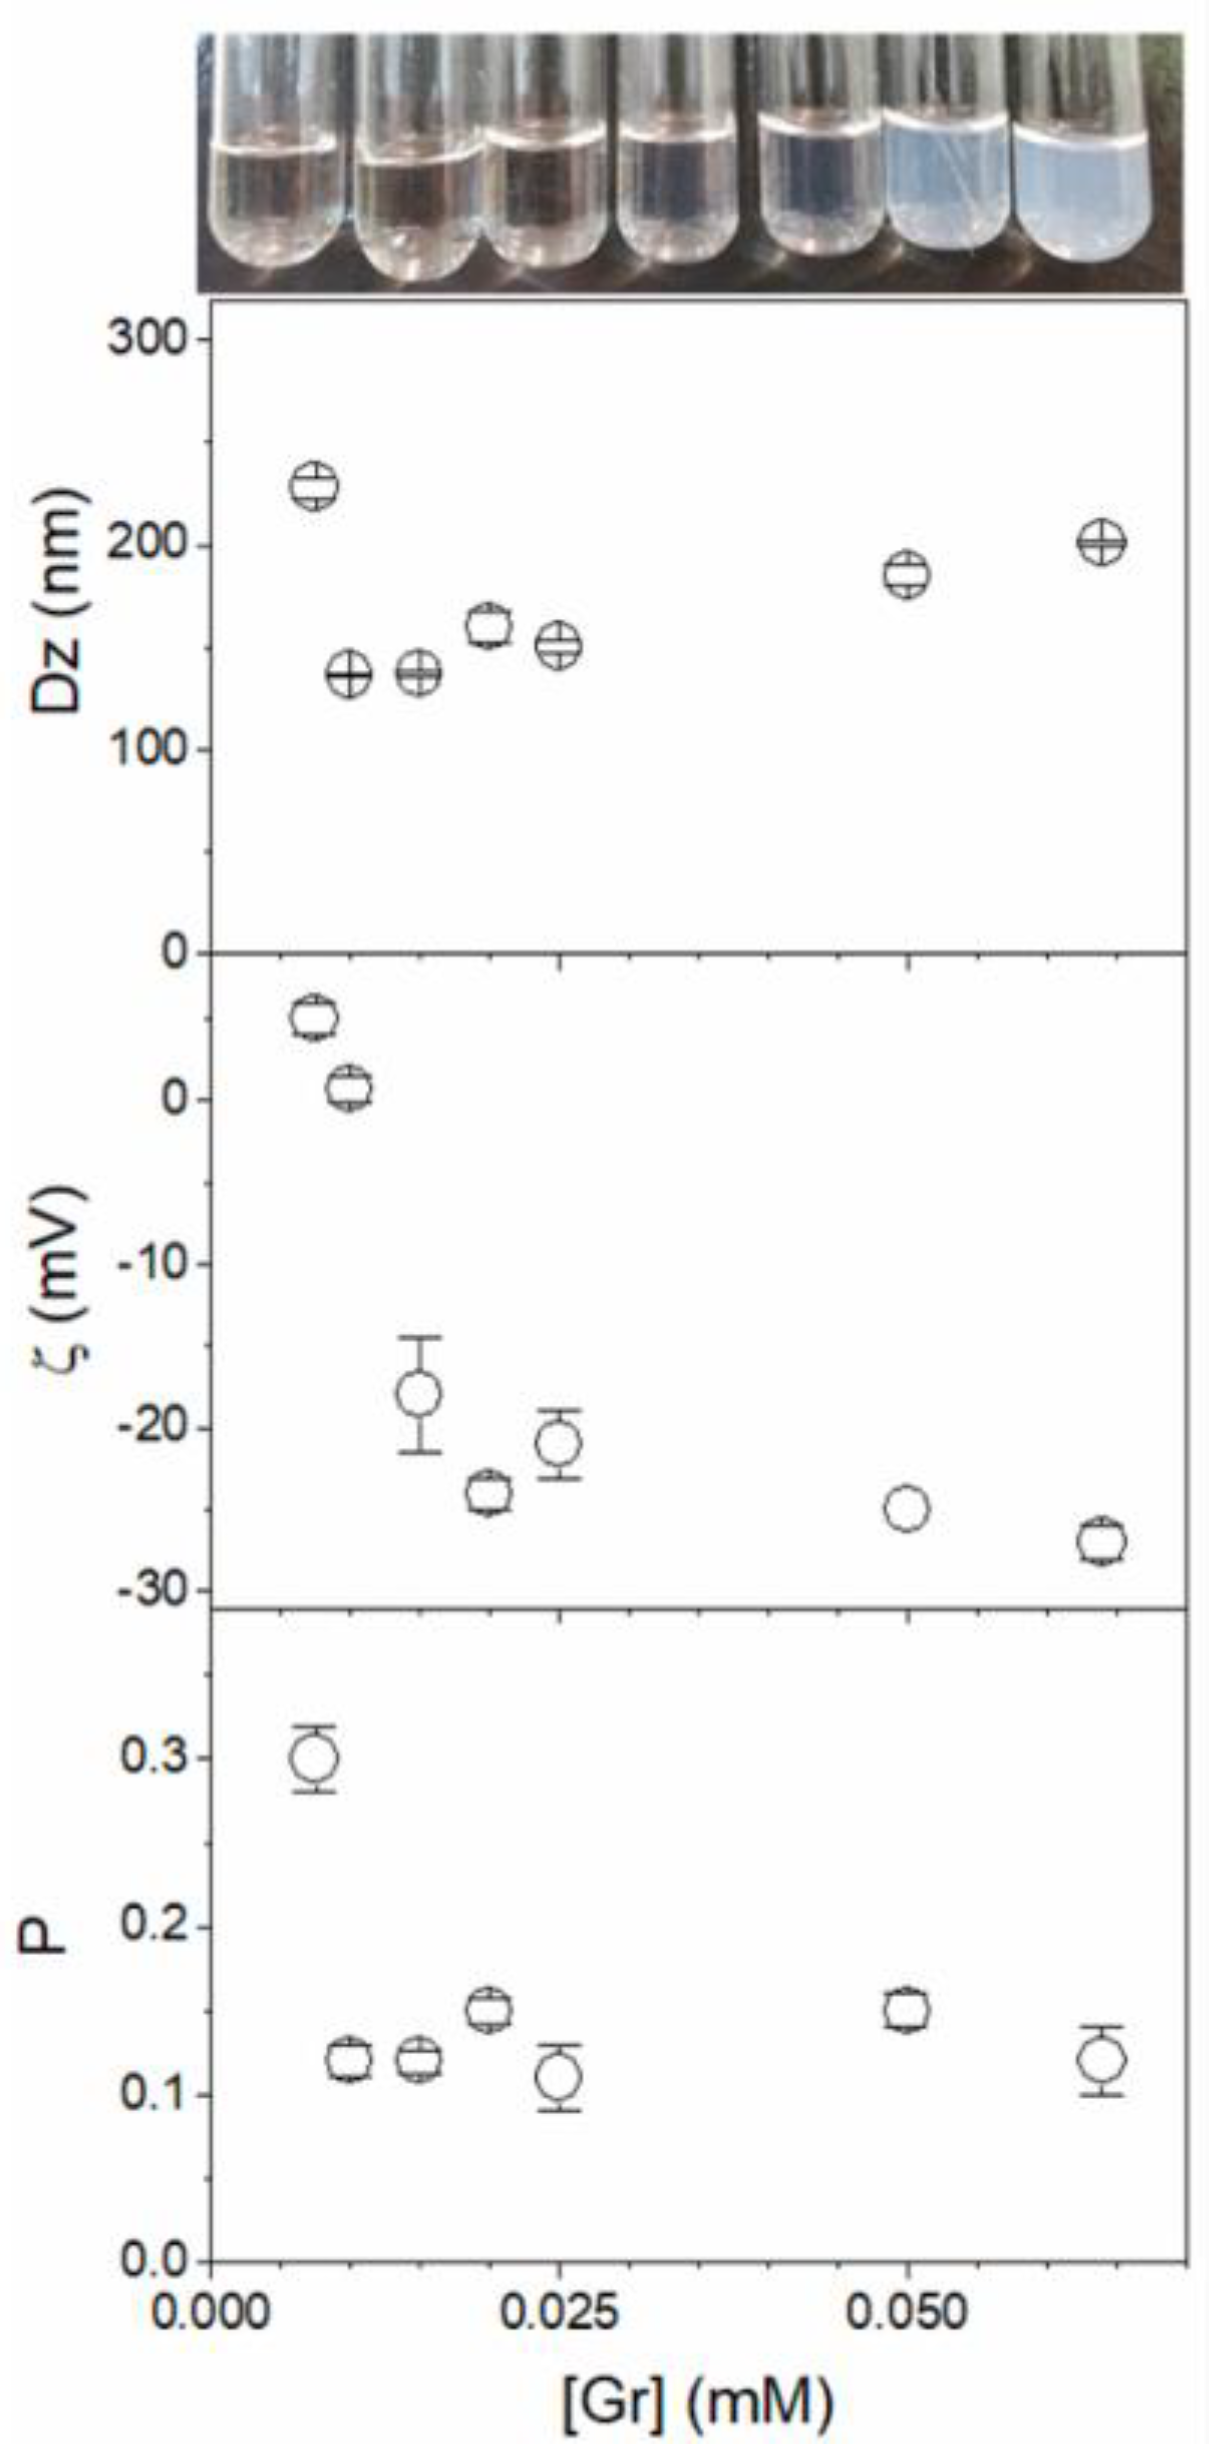

3. Gramicidin D and Its Assemblies